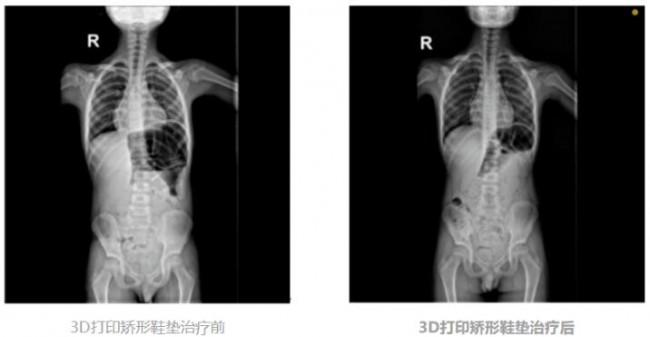

案例一:患者朱某,男性,11岁,鞋垫穿戴时间8个月余,有效改善后跟外翻及脊柱侧凸。